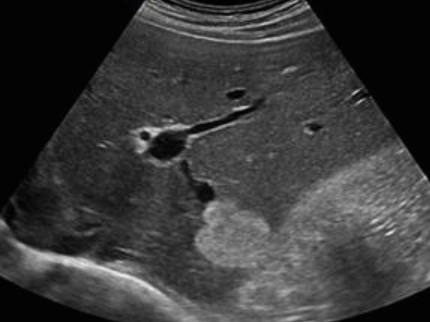

US finding

- (초기) 경계가 분명한 원형, 타원형 종괴로 내부에코는 저에코이다.

- (후기) 진행될수록 무에코로 변한다.

- location: 간표면 근처

amoebic abscess 2) 기생충성이 아닌 간낭종 (non-parasitic )